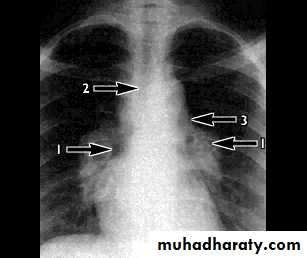

Chest X-rayLower zone shadowing

Decreased lung size

- Bilateral hilar lymphadenopathy , asymptomatic, subside without treatment in about 80-90% of patients

- Pulmonary infiltration and bilateral hilar lymphadenopathy which may cause symptoms such as dyspnoea, cough and fever, but subsides in 40% of patients

Pulmonary infeltrate

Hilar adenopathy